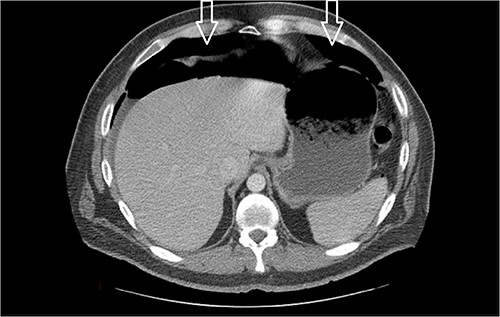

Dietary consultation started him on a gastroparesis diet where he progressed well. Upon hospital discharge CT showed a moderate volume of pneumoperitoneum with a small volume of perihepatic and perisplenic ascites. No areas of focal bowel wall thickening were noted (see Fig. 4).

Similar appearance of moderate volume pneumoperitoneum compared with last CT.